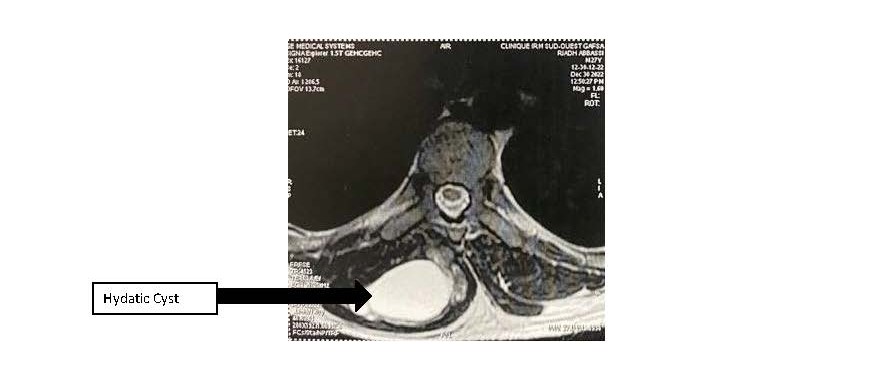

In order to study the ratios of the mass more closely, an MRI scan was carried out, which revealed a right paramedian intermuscular fluid formation located between the erector spinae muscles on the inside and the trapezius on the outside, with a fusiform shape measuring 96 mm in height and 52 x 30 mm in larger dimensions in the axial plane. This formation has a multiloculated appearance and does not show any significant enhancement after injection of gadolinium. This mass initially suggests a hydatid origin (Figure 1). The hydatid serology was positive, and the TAP CT did not reveal any other sites of disease. The patient had monobloc excision of the cyst with no intraoperative rupture (Figure 2 and Figure 3) and the postoperative course was uncomplicated. Histological examination confirmed the diagnosis of a muscular hydatid cyst. At the 6-month and 1-year follow-up, clinical, biological, and ultrasonographic evaluations revealed no evidence of local or visceral recurrence.

Figure 1. MRI showing multiloculated cyst.

In the present case, ultrasound facilitated the initial diagnosis, revealing features suggestive of either hydatidosis or a benign tumor. The diagnosis of hydatid disease was subsequently confirmed by MRI.